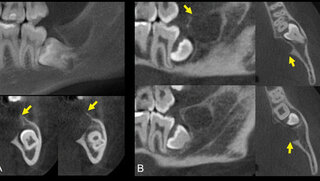

Case ReportTumor imitiert odontogene Läsion Eine vermeintlich odontogene Läsion ausgehend von einem Unterkiefer-Weisheitszahn stellt sich als seltene Tumorentität heraus. 10.11.2023 Zahnmedizin